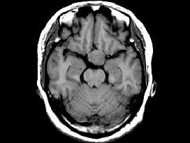

女,38岁,左侧视力下降伴头昏1个月余,根据所提供图像,最可能的诊断是()

女,38岁,左侧视力下降伴头昏1个月余,根据所提供图像,最可能的诊断是()

[单选题]女,38岁,左侧视力下降伴头昏1个月余,根据所提供图像,最可能的诊断是()A . 颅咽管瘤B . 垂体嫌色细胞腺瘤C . 视神经胶质瘤D . 软骨瘤E . 脑膜瘤